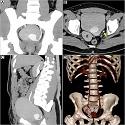

Prostatic fossa calculus

Yassine El Abiad, Mohammed Alami

PAMJ. 2015; 21: 236. Published 31 July 2015